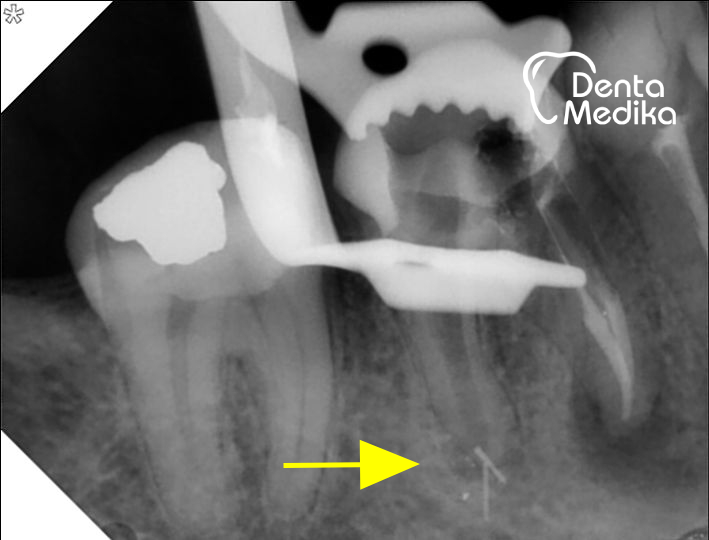

Nekvalitní zaplnění Reendodoncie - u stejného

kořenových kanálků zubu kanálky pročištěny

- v nedoplněných a znovu zaplněny - přesně,

místech přežívají až po hroty kořenů

bakterie